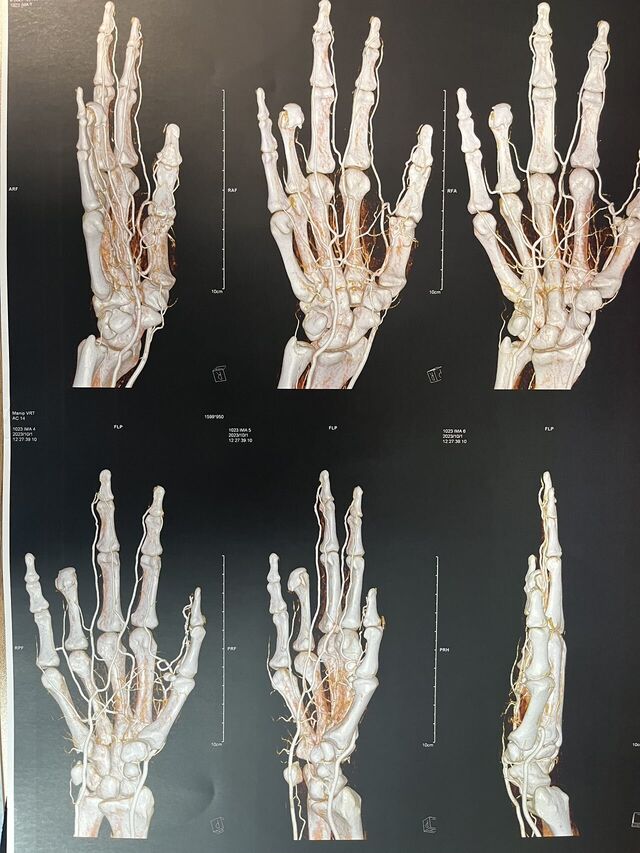

昨天的手术。

微信图片_20231008195909.jpg 微信图片_20231008195912.jpg 微信图片_20231008195906.jpg 微信图片_20231008195903.jpg 微信图片_20231008195829.jpg 微信图片_20231008195839.jpg 微信图片_20231008195836.jpg 微信图片_20231008195945.jpg 微信图片_20231008195939.jpg